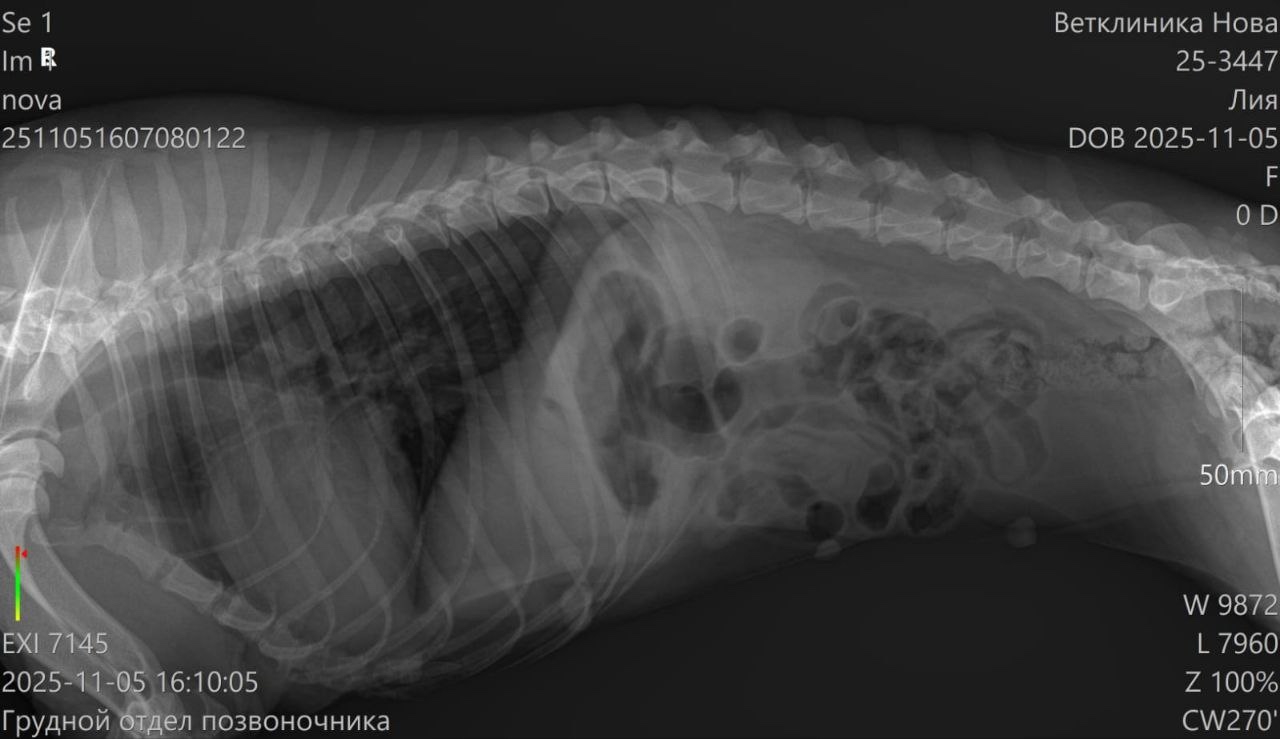

Девчонка не встает на задние лапы,чувствительности нет. Сделали рентген,по снимку у Леи сломано ребро(травма старая,органы не задевает,поэтому трогать ее не нужно.)

🙏Явно что-то с позвоночником,но без МРТ просто по рентгену врач не видит,что с ним.